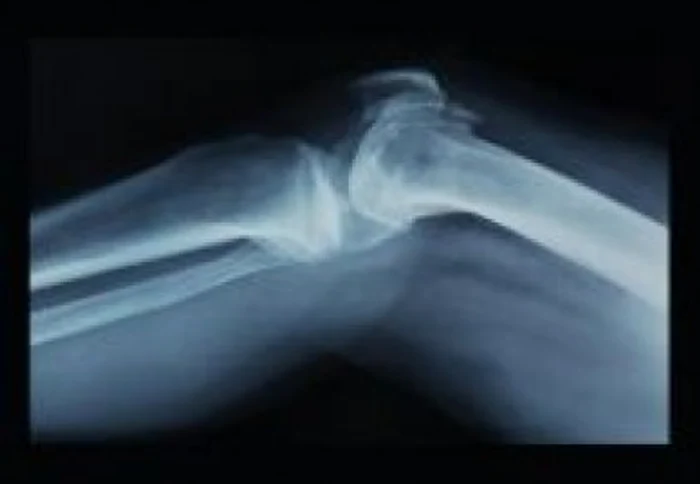

Noua tehnică pentru ortopedia pediatrică este miniinvazivă şi constă într-o mică incizie care permite introducerea unei tije centro-medulare pe osul fracturat, sub control radiologic. Această procedură modernă înlocuieşte vechile metode de intervenţie chirurgicală şi asigură recuperarea post operatorie mult mai rapidă, iar acesta poate să plece acasă după două zile de la intervenţie.